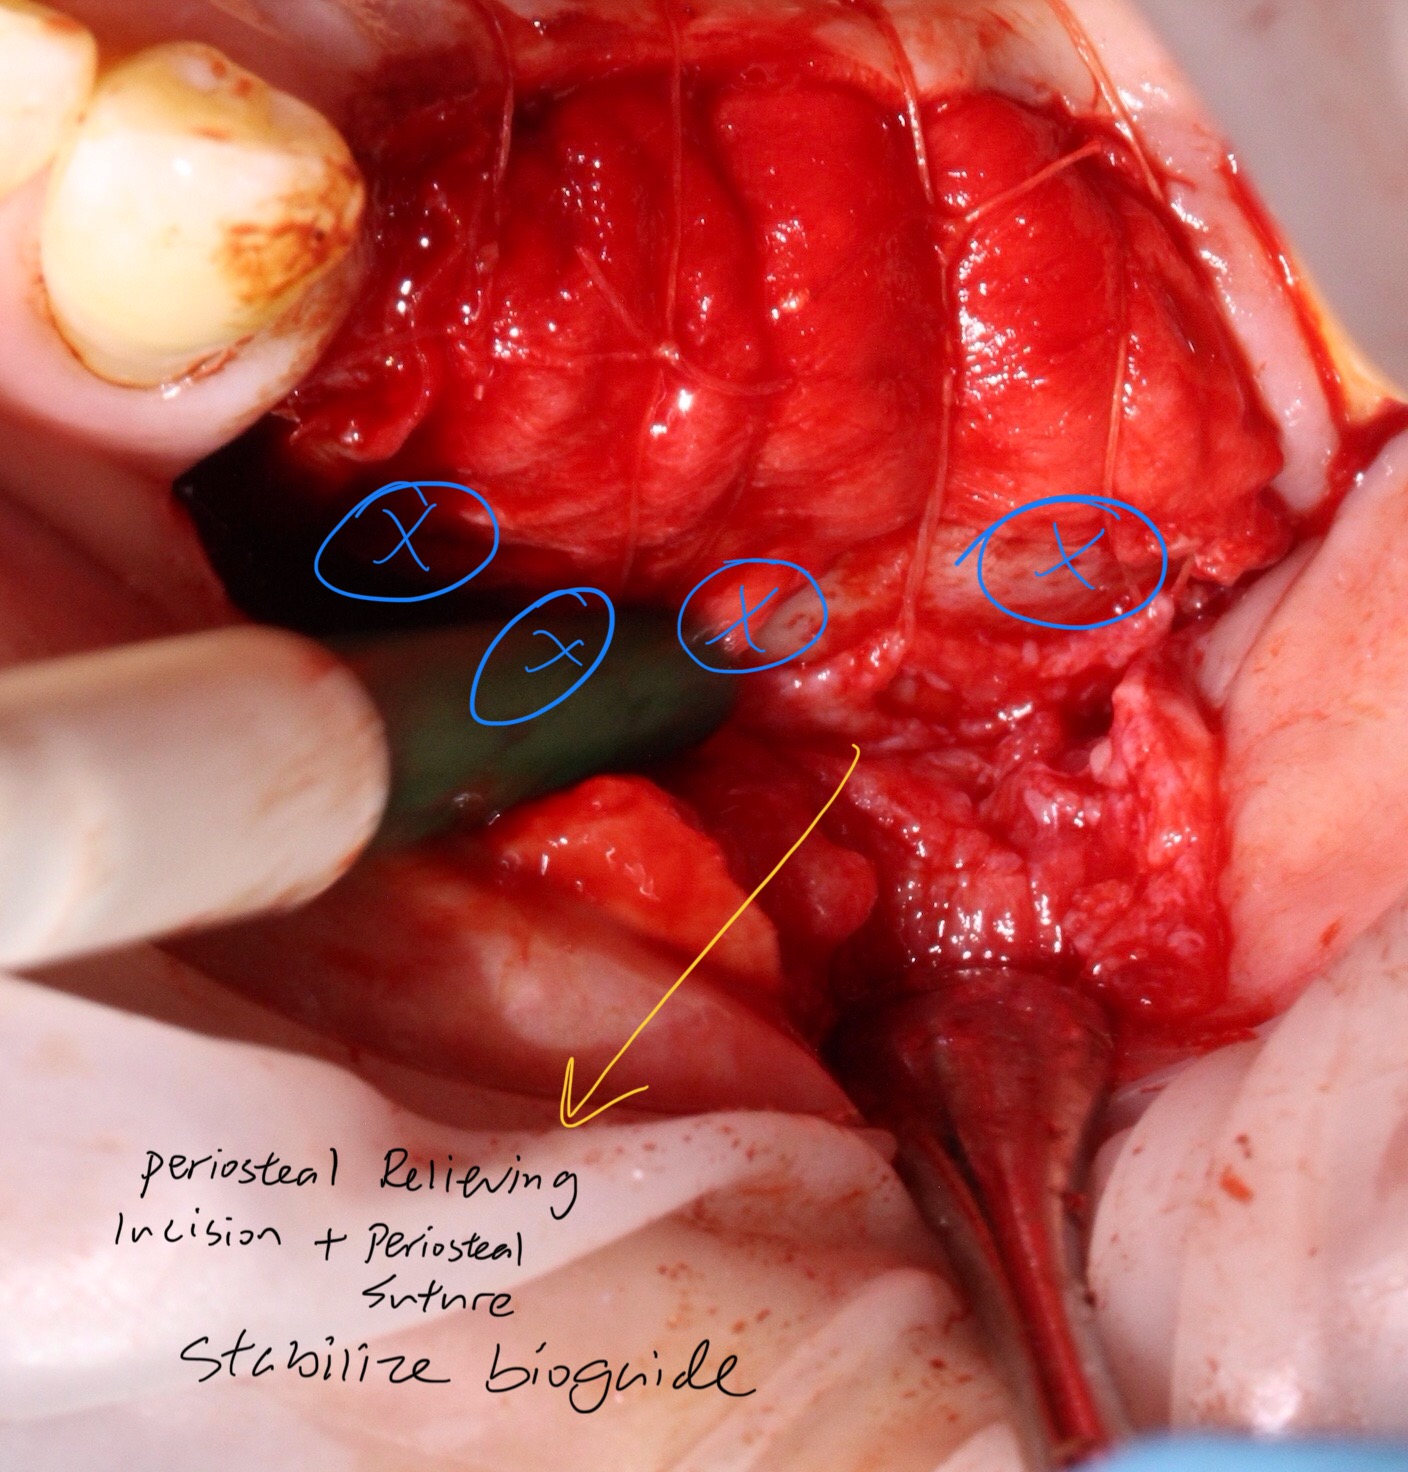

with buccal relieving periosteal incision and BIO OSS and puro OSS (allograft + xenograft ) added under bioguide

( not sure if the blue region should be where tacks needs to be placed. I did not use tacks as I was a bit scared. just suture only